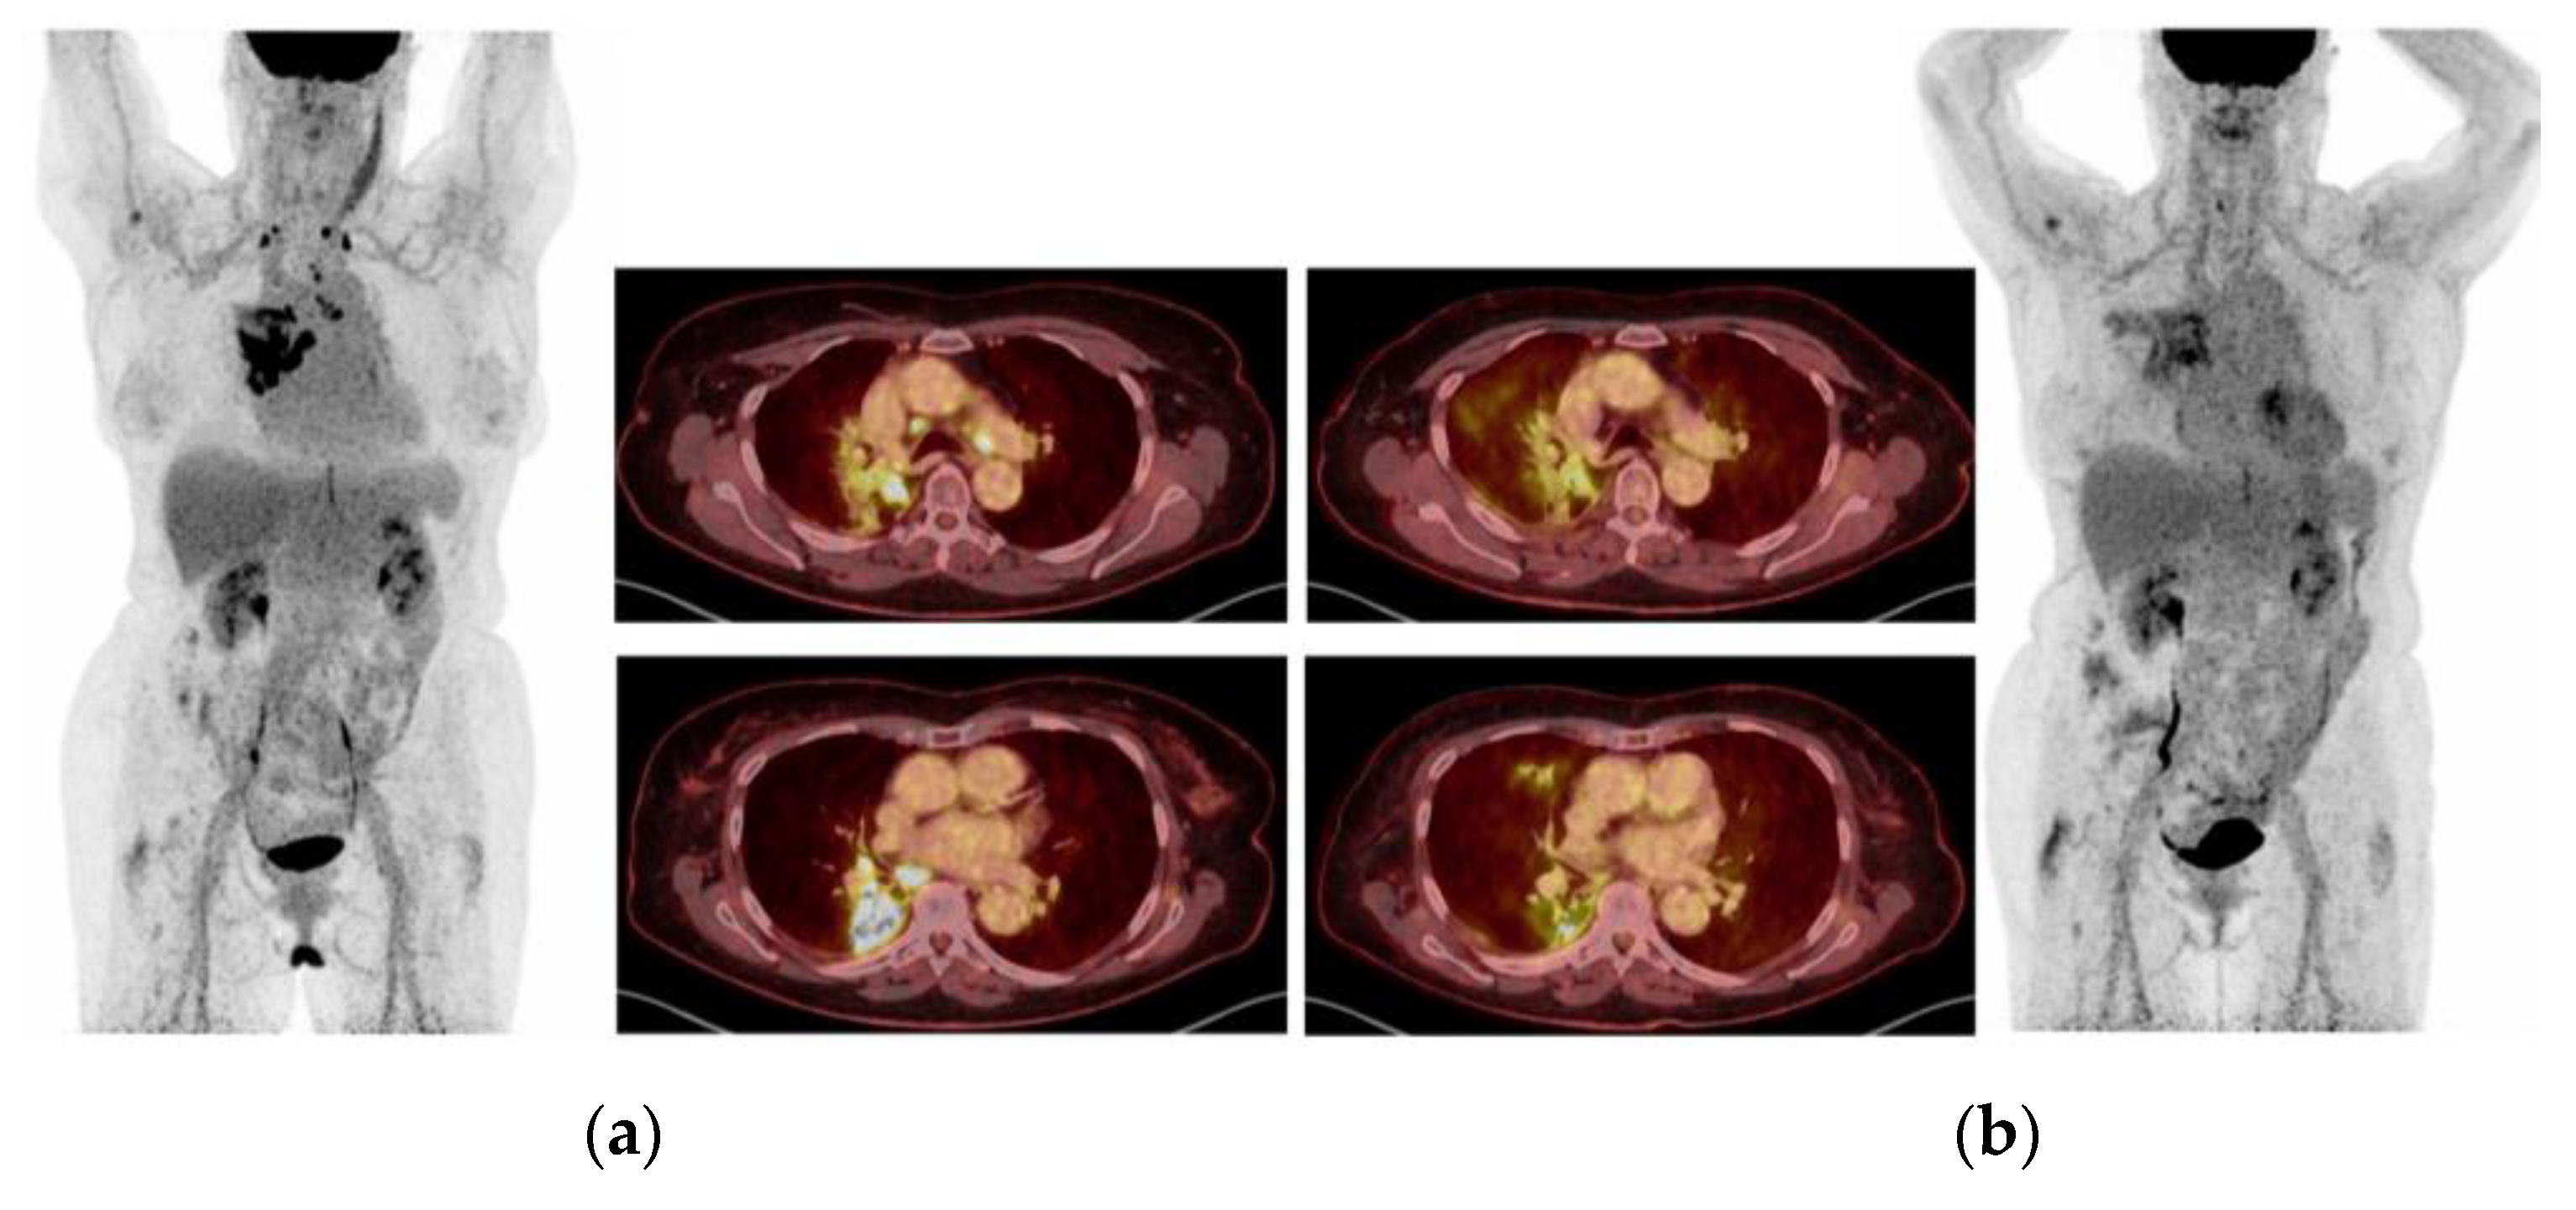

2.4. Case 4: Durable Response of Metastatic EGFRm+ NSCLC to Fourth Line Gefitinib Rechallenge Combined with Crizotinib Because of Acquired High-Level MET Amplification

2.5. Case 5: Efficacy of Crizotinib-Osimertinib in EGFRm+ NSCLC Patient Acquiring High-Level MET Amplification after 26 Months of Treatment with Osimertinib